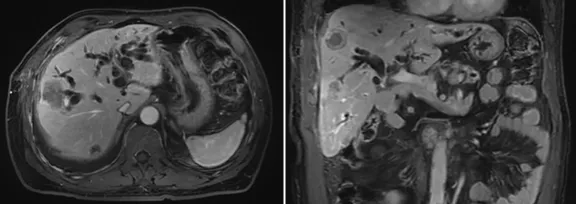

6月復查,上腹部MRI提示考慮肝內(nèi)多發(fā)轉(zhuǎn)移,行標準治療,予全身化療;

增強CT結(jié)果

壺腹部腺癌術(shù)后改變,左右肝管匯合部異常信號,不除外復發(fā)可能;考慮肝內(nèi)多發(fā)轉(zhuǎn)移瘤形成

所見右側(cè)胸腔積液,右下肺片狀異常信號,建議進一步胸部檢查